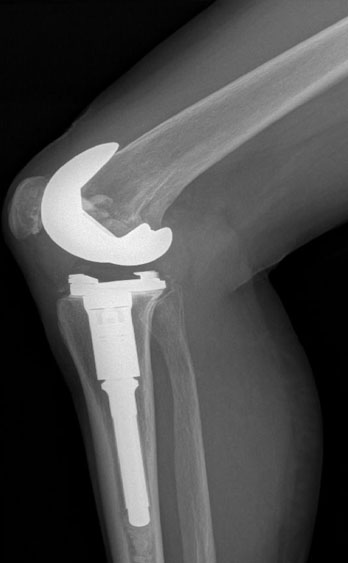

SICAPS, Es una empresa joven, la cual se creó después de trabajar en una compañía para el cuidado de la salud con la

confianza de estar estructurada y dirigida por especialistas en venta de productos quirúrgicos y técnicos especializados en

la salud, que se unificaron para ofrecer una satisfacción total; ya que se cuenta con los materiales, productos y

herramientas de la más alta calidad, con un servicio de primera. Nuestro personal está permanentemente actualizándose.

Hoy en día SICAPS ofrece productos, materiales quirúrgicos a personas particulares y empresas del giro hospitalario,

salud.